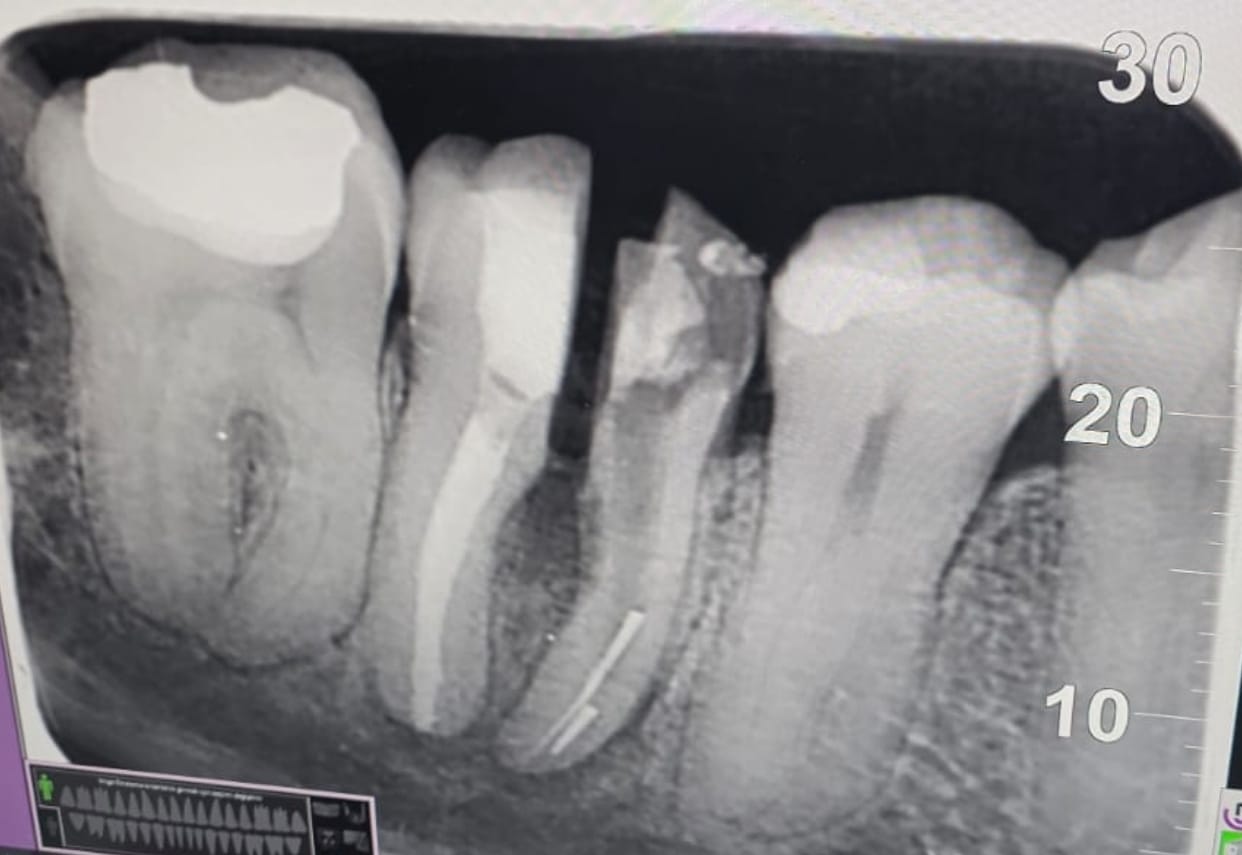

Meğer dişte üç kök varmış. Aletin kırıldığı ve yanındaki küçük kökün bulunduğu taraf kesilip çekilecek, kalan büyük kök üzerine kaplama yapılacakmış. Dişin yarısını doğal bir implant gibi düşünün. İmplant yaptıranlar sürecin ne kadar rahatsızlık verici olduğunu bilirler. Maddi karşılığından bahsetmiyorum bile. Neyse, diş filmini de aşağıda paylaşıyorum; içerideki kırık aleti net şekilde görebilirsiniz.